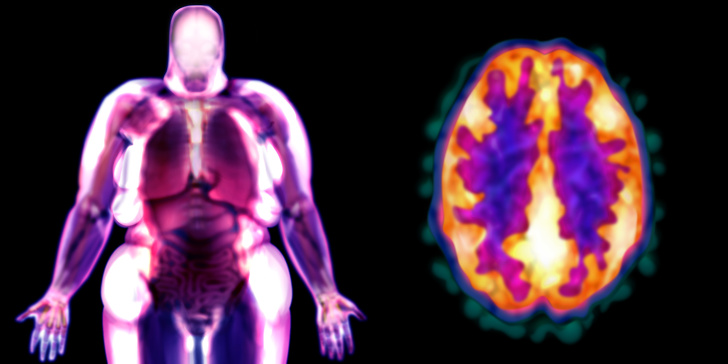

Τα σώματά μας αρχίζουν να αναπτύσσονται και να αλλάζουν χάρη σε σήματα από ορισμένα είδη ορμονών. Κανονικά, οι ορμόνες μας βοηθούν να ελέγξουμε πόσες θερμίδες διατηρούμε για ενέργεια και πόσες πρέπει να κάψουμε αμέσως.

Αποδεικνύεται ότι πολλές από τις χημικές ουσίες από τη βιομηχανία στο περιβάλλον μοιάζουν επίσης με ορμόνες. Και αυτές οι χημικές ουσίες μπορούν να προκαλέσουν την ίδια απάντηση στο σώμα μας, όπως οι φυσικές ορμόνες. Με άλλα λόγια, λειτουργούν σχεδόν με τον ίδιο τρόπο.

Οι χημικές ουσίες μπορούν να αναγκάσουν το σώμα να “σκέφτεται” ότι πρέπει να κρατήσει περισσότερο λίπος από ό, τι πραγματικά χρειάζεται. Επίσης, παρεμβαίνουν στη διαδικασία παραγωγής λιπωδών κυττάρων.